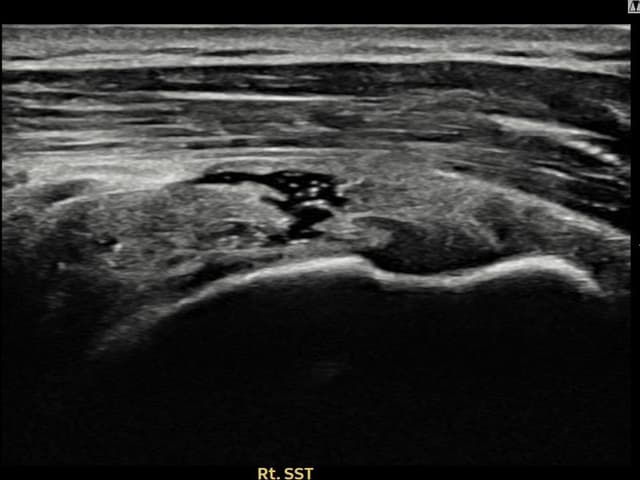

右侧 冈上肌腱 石灰化肌腱炎

14mm × 10mm